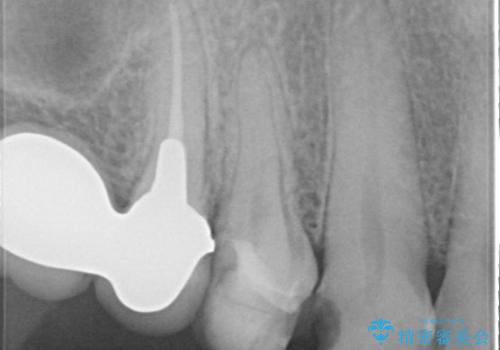

- 以前治療したセラミックインレーが破折したことを主訴に来院されました。

咬合力が強く、残存歯質が少ないためオールセラミッククラウンによる治療を行いました。

今回は白い材料での修復を希望されたため、欠けるリスクが高いセラミックインレーは避け、セラミッククラウンにて治療を行いました。